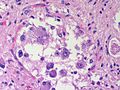

| Glioblastoma (WHO grade IV) | glial processes (esp. on smear), nuclear atypia (typical size var. ~3x, irreg. nuc. membrane, hyperchromasia), no Rosenthal fibres in the core of the lesion †, microvascular proliferation or necrosis | often enhancing (suggests high grade), usu. supratentorial, usu. white matter | usu. old, occ. young | very common, esp. glioblastoma | IDH-1+/-, GFAP+ | |

Microvascular proliferation or necrosis with pseudopalisading tumour cells:

- Grade IV (glioblastoma AKA glioblastoma multiforme).

Notes:

- Pseudopalisading tumour cells = high tumour cell density adjacent to regions of necrosis; palisade = a fence of poles forming a defensive barrier or fortification.

Glioblastoma: